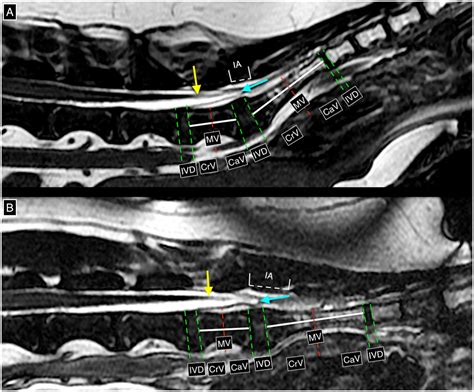

Tethered Cord MRI plays a pivotal role in the diagnosis of tethered cord syndrome. This imaging technique uses magnetic fields and radio waves to produce detailed images of the spinal cord and surrounding structures. Unlike traditional MRI, Tethered Cord MRI focuses specifically on the spinal cord, providing high-resolution images that can detect even the slightest abnormalities.

One of the key advantages of Tethered Cord MRI is its ability to visualize the spinal cord in multiple planes. This allows radiologists to get a comprehensive view of the spinal cord and identify any areas where it may be tethered. The images obtained from Tethered Cord MRI are also highly detailed, making it easier to pinpoint the exact location and extent of the tethering.

After the Tethered Cord MRI procedure, the images will be reviewed by a radiologist who specializes in interpreting MRI scans. The radiologist will look for signs of tethered cord syndrome, such as:

• Thickened Filum Terminale: The filum terminale is a thin, fibrous structure that anchors the spinal cord. In tethered cord syndrome, this structure may be thickened or shortened.

• Spinal Cord Stretching: The spinal cord may appear stretched or elongated, indicating that it is being pulled down by the tethering.